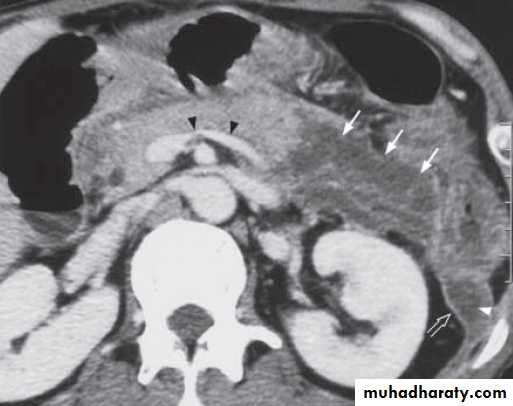

Contrast enhanced axial computed tomography (CT) shows a pancreatic abscess (arrows) appearing as a multiple loculated hypodense lesion with a thick enhancing wall.

Contrast enhanced axial computed tomography (CT) showing a small pancreatic pseudocyst (arrow) in pancreatic tail in a patient with recent history of pancreatitis.

Contrast enhanced axial computed tomography (CT) shows non-enhancement of the swollen pancreatic body and tail (arrows) compatible with pancreatic necrosis.